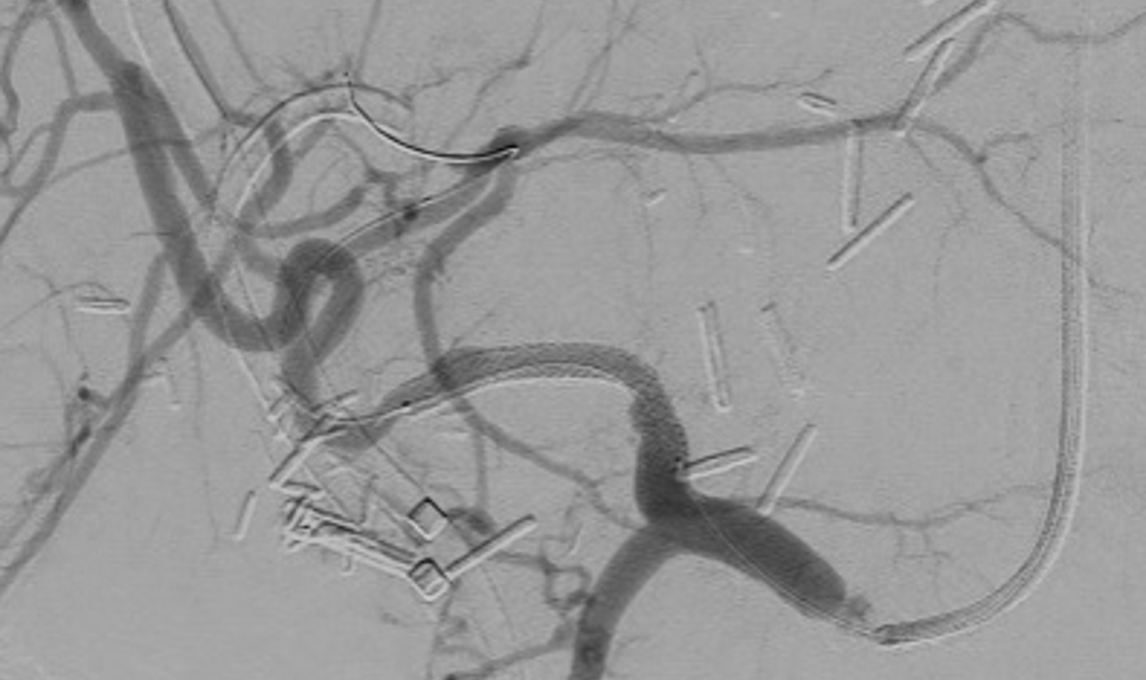

Stent placement is a suboptimal mechanical solution to chronic venous disease. We are doing translational research using a sheep model to study potential gene therapy strategies to minimize post-thrombotic venous changes and ameliorate the downstream quality-of-life complications.

Our research utilizes advanced flow imaging and computational fluid dynamics modeling to map complex blood flow patterns in healthy, diseased, and stented veins. We aim to uncover how chronic venous disease and interventions like stent placement alter hemodynamics, providing critical insights to optimize treatments for conditions like iliac vein compression (May-Thurner) syndrome and post-thrombotic sequelae.